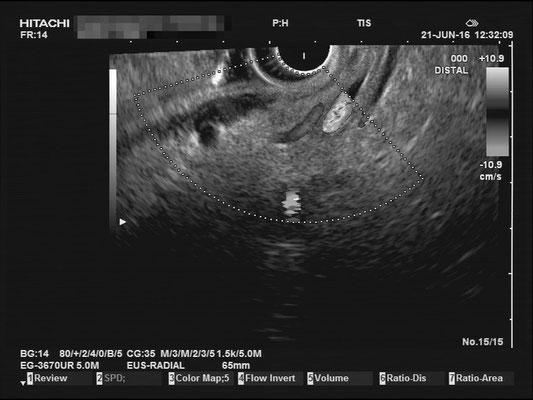

For a full examination of the common bile duct (CBD), we want have a great view of the most distal part, at the duodenal papilla. Optimally we can identify the double duct sign (or as I like to call it the "money shot") and work our way towards the liver. The CBD is joined by the hepatic artery and Portal vein, making up the Glisson's Triad. Using the doppler signal will help differentiate the vessels.

The most observant viewers will have noticed that not all images above depict normal findings but some abnormalities. (my bad ;)